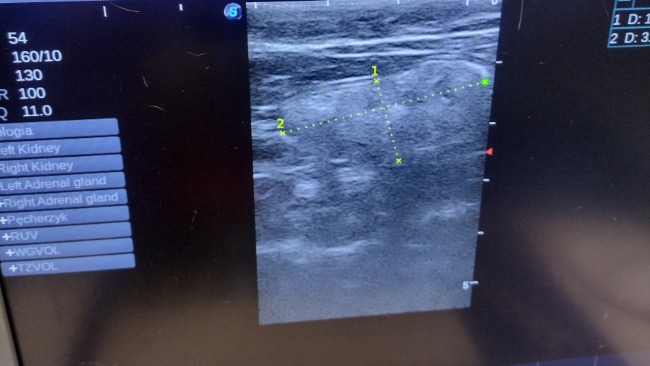

Zabraliśmy kotka na badania krwi. Przy okazji okazało się, iż zęby są w bardzo złym stanie i w tym tygodniu kotek przejdzie sanację zębów oraz badanie usg.

Koszt sanacji zębów to około 400 zł. Dodatkowo musimy wykonać badanie krwi na krzepliwość, wykonano usg jamy brzusznej, kotek ma powiększone jelito, zapisane są leki na tydzień i za tydzień kontrola.